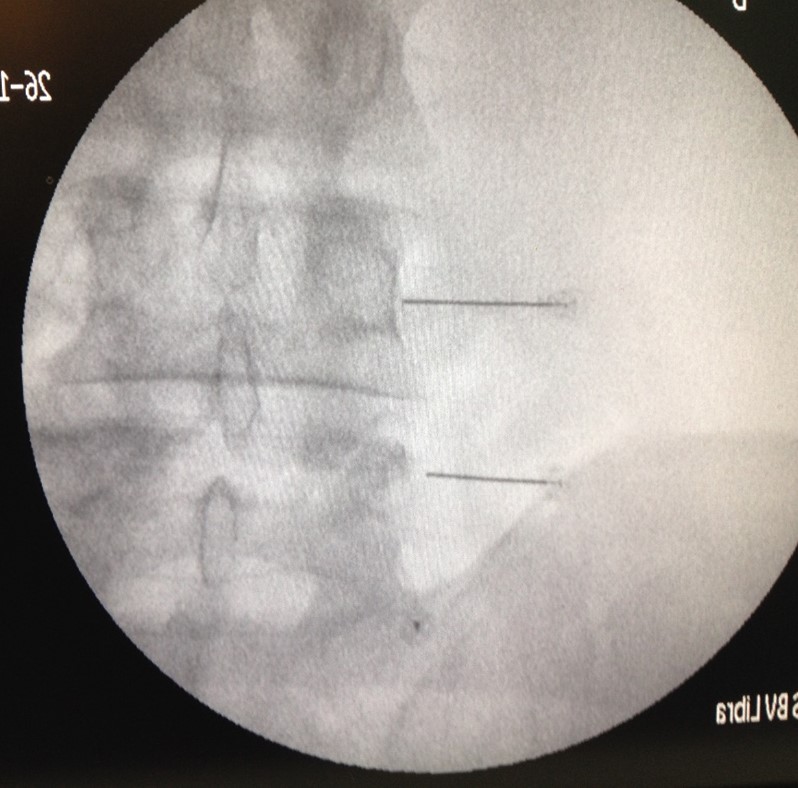

Si realizamos un buen diagnóstico clínico y confirmamos con una exploración, casi siempre podemos realizar un bloqueo facetario de prueba que nos serviría como conformación del diagnóstico y muchas veces como único tratamiento.

MRG es una paciente de 44 años, deportista, activa, aunque con un trabajo de oficina de varias horas al día en sedestación. Comenzó con un dolor lumbar localizado después de un pequeño esfuerzo al mover unos muebles en casa.

Acudió a su médico que aconsejo, antiinflamatorios y reposo. Después al no mejorar le aconsejaron usar indometacina en inyecciones durante diez días una cada día, obteniendo una mínima mejoría que desapareció al concluir.

Contactó con nosotros remitido para una segunda opinión y le explicamos nuestro punto de vista. Nos pidió una prueba de imagen para descartar otra patología y en ella apreciamos artrosis degenerativa en las articulaciones vertebrales lumbares L4-L5-S1 con predominio derecho, y protrusión discal leve a dichos niveles sin otros hallazgos.

Aconsejamos bloqueo facetario que realizamos bajo control radiológico con éxito. La paciente obtuvo un beneficio casi inmediato durante aproximadamente un mes.

La reaparición de la molestia nos orientó a repetir el bloqueo con radiofrecuencia con un éxito semejante pero mucho más prolongado en el tiempo. El bloqueo de la rama medial de la raíz dorsal que inerva la articulación suele generar un bloqueo duradero y casi completo.

Completamos el bloqueo con las recomendaciones habituales de higiene postural, vida activa, ergonomía y pérdida de peso.

La paciente se mantiene casi asintomática desde hace un año, ya sabe que no está curada, que no se ha convertido en otra persona con el bloqueo y que depende de su estilo de vida que no reaparezcan los síntomas. Nuestra labor consiste en darle el empujón necesario para el coche sin batería arranque, pero recargar la batería primero y evitar que se descargue, después, depende fundamentalmente de ella.